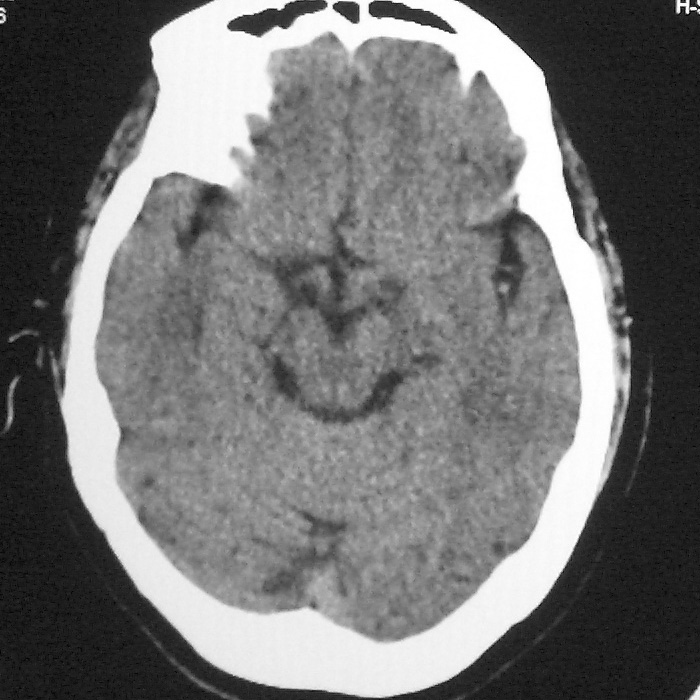

f,70y,口角歪斜、流涎、吐词不清三天

左侧大脑基底节区点状低密度影,边缘清楚,左侧腔梗或软化灶,没什么问题啊?

症状这么明显的话一般不会是单纯面神经麻痹引起的,最好做个mri,如果确实没有问题的话才能考虑面神经麻痹,毕竟这两种病的治疗和预后不一样,这个病人还有脑白质疏松。

左侧半卵圆中心腔梗应当比较明确,右侧基底节好象不明显,不好说,做个mri明确吧

双侧多发腔梗

右侧基底,左侧半卵圆中心腔梗

1、右侧基底,左侧半卵圆中心腔梗。2脑萎缩。

左侧腔隙性梗塞灶,脑萎缩。

左侧基底节区示点状低密度灶,边界清楚,密度均匀,余所示无著变。

意见:腔隙性脑梗塞(左基底节区)

各位老师,报告这么写可以吗?右侧我没有看出来。

左侧半卵圆中心,右侧基底节腔梗。再加个脑萎缩吧

双侧多发腔梗 脑萎缩